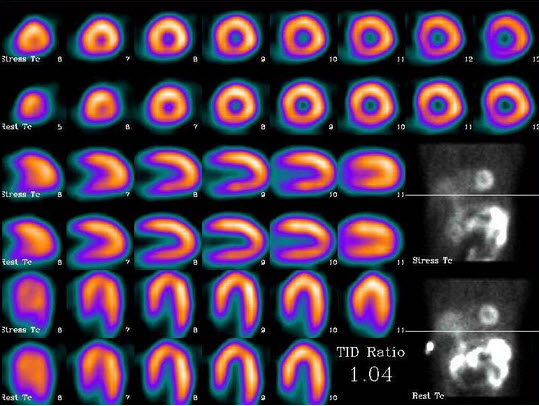

51、单项选择题

33岁男性,阵发性高血压2年,行I-MIBG腹部平面显像如图,最可能的诊断是()

A.双侧肾上腺髓质增生

B.双侧肾上腺嗜铬细胞瘤

C.大致正常的肾上腺髓质影像

D.双侧肾上腺皮质增生

E.右侧腹主动脉旁异位嗜铬细胞瘤